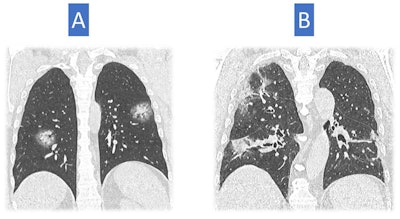

Italy

Italy was quite hard hit, said Dr. Nicola Sverzellati, head of the radiology unit at the University Hospital of Parma. The country's first patient, a 38-year-old man, presented at an emergency department in Codogno in February with acute respiratory distress syndrome. Only a few weeks later, the government locked Codogno and neighboring villages down. As the virus spread through the country, clinicians across Italy began tracking chest CT features of COVID-19, including ground-glass opacities, multilobe involvement, bilateral distribution, and posterior involvement.